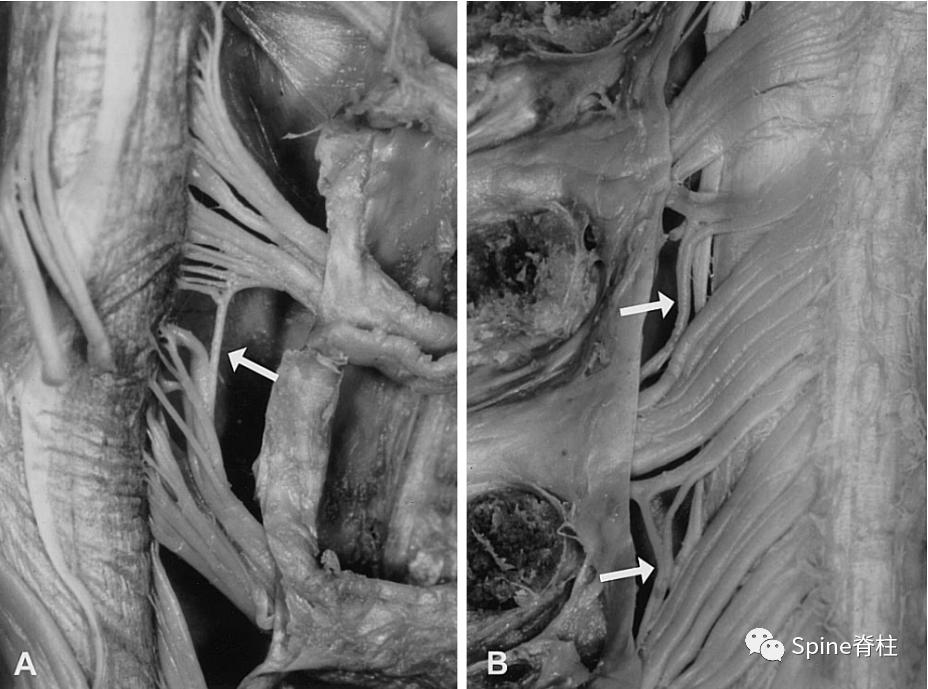

图: 解剖研究发现两个颈神经根之间存在 鞘内节段间吻合支 (箭头, PMID: 10703098)。使得一个背根节内的感觉神经元可通过不同节段进入脊髓。 61%的颈椎、7%的胸椎和 22%的腰椎背根内发现鞘内节段间吻合 。因此,上肢皮节的个体变异要多于其他部位。